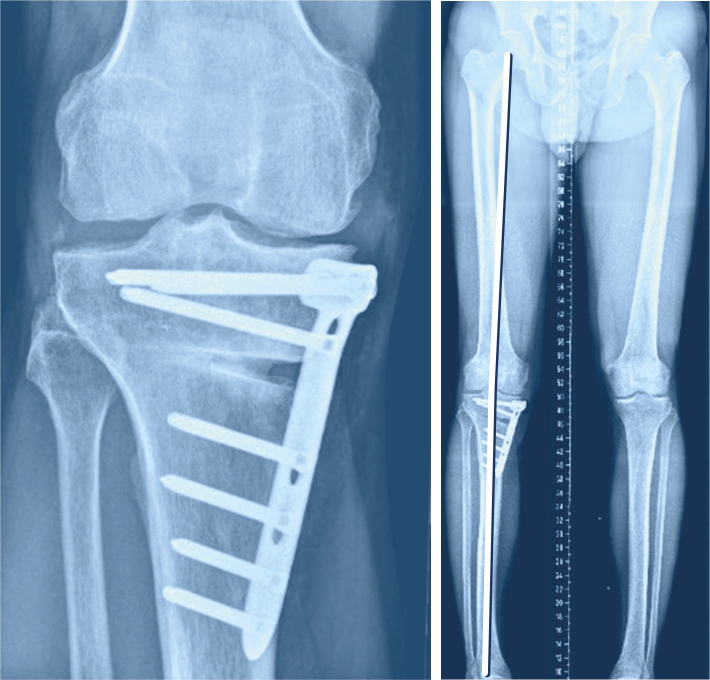

Wenn nur auf der Innen- oder der Aussenseite des Kniegelenks eine Arthrose vorliegt, kann mit einer sogenannten Umstellungsosteotomie oft eine Linderung der Beschwerden über Jahre erzielt werden, ohne dass ein künstliches Gelenk eingebaut werden muss. Wenn nur die Innenseite des Kniegelenks von der Arthrose betroffen ist (O-Beine), während die äussere Gelenkhälfte völlig schmerzfrei ist, kann mittels Umstellungsosteotomie durch eine Knochendurchtrennung im oberen Schienbeinbereich ein leichtes X-Bein erzielt werden (sogenannte Valgisationsosteotomie), was zur Entlastung der inneren Gelenkhälfte führt. Ziel ist es, unter Erhalt des eigenen Gelenks die Schmerzen zu vermindern und das Fortschreiten der Arthrose aufzuhalten oder zumindest zu verzögern. Zur Behandlung der Valgusgonarthrose (X-Fehlstellung) erfolgen Knochendurchtrennung und Achsenkorrektur knienah meistens am Oberschenkel (Varisationsosteotomie). Ist die Fehlstellung sehr ausgeprägt ist es manchmal sogar notwendig, in derselben Operation am Ober- und Unterschenkel einen Korrektureingriff vorzunehmen.

Bei der Valgisationsosteotomie wird der Knochen über einen Hautschnitt an der Innenseite des Kniegelenks durchgesägt und in der neuen aufgespreizten Position mit einer Platte und Schrauben fixiert. Der durch das Aufklappen entstehende Zwischenraum wird gelegentlich mit Knochen aus dem Beckenkamm gefüllt. Die endgültige Stabilität erhält der Knochen jedoch erst durch die Knochenheilung. Der Patient muss das operierte Bein während 6 Wochen durch Gehstöcke entlasten. In dieser Phase ist zudem eine Blutverdünnung notwendig, um das Risiko einer Venenthrombose oder einer Lungenembolie so gering wie möglich zu halten. Zeigt die Röntgenkontrolle im Verlauf der Nachbehandlung einen zunehmenden Durchbau des Knochens an der Stelle, an der er durchtrennt wurde, kann die Belastung gesteigert werden. Häufig ist nach 10 bis 12 Wochen wieder die volle Belastung möglich.

Muss die Korrektur knienah am Oberschenkel durchgeführt werden, erfolgt der Hautschnitt weiter oben an der Innenseite des Oberschenkels. Die Operationstechnik an sich sowie die Nachbehandlung sind bei beiden Eingriffen ähnlich.